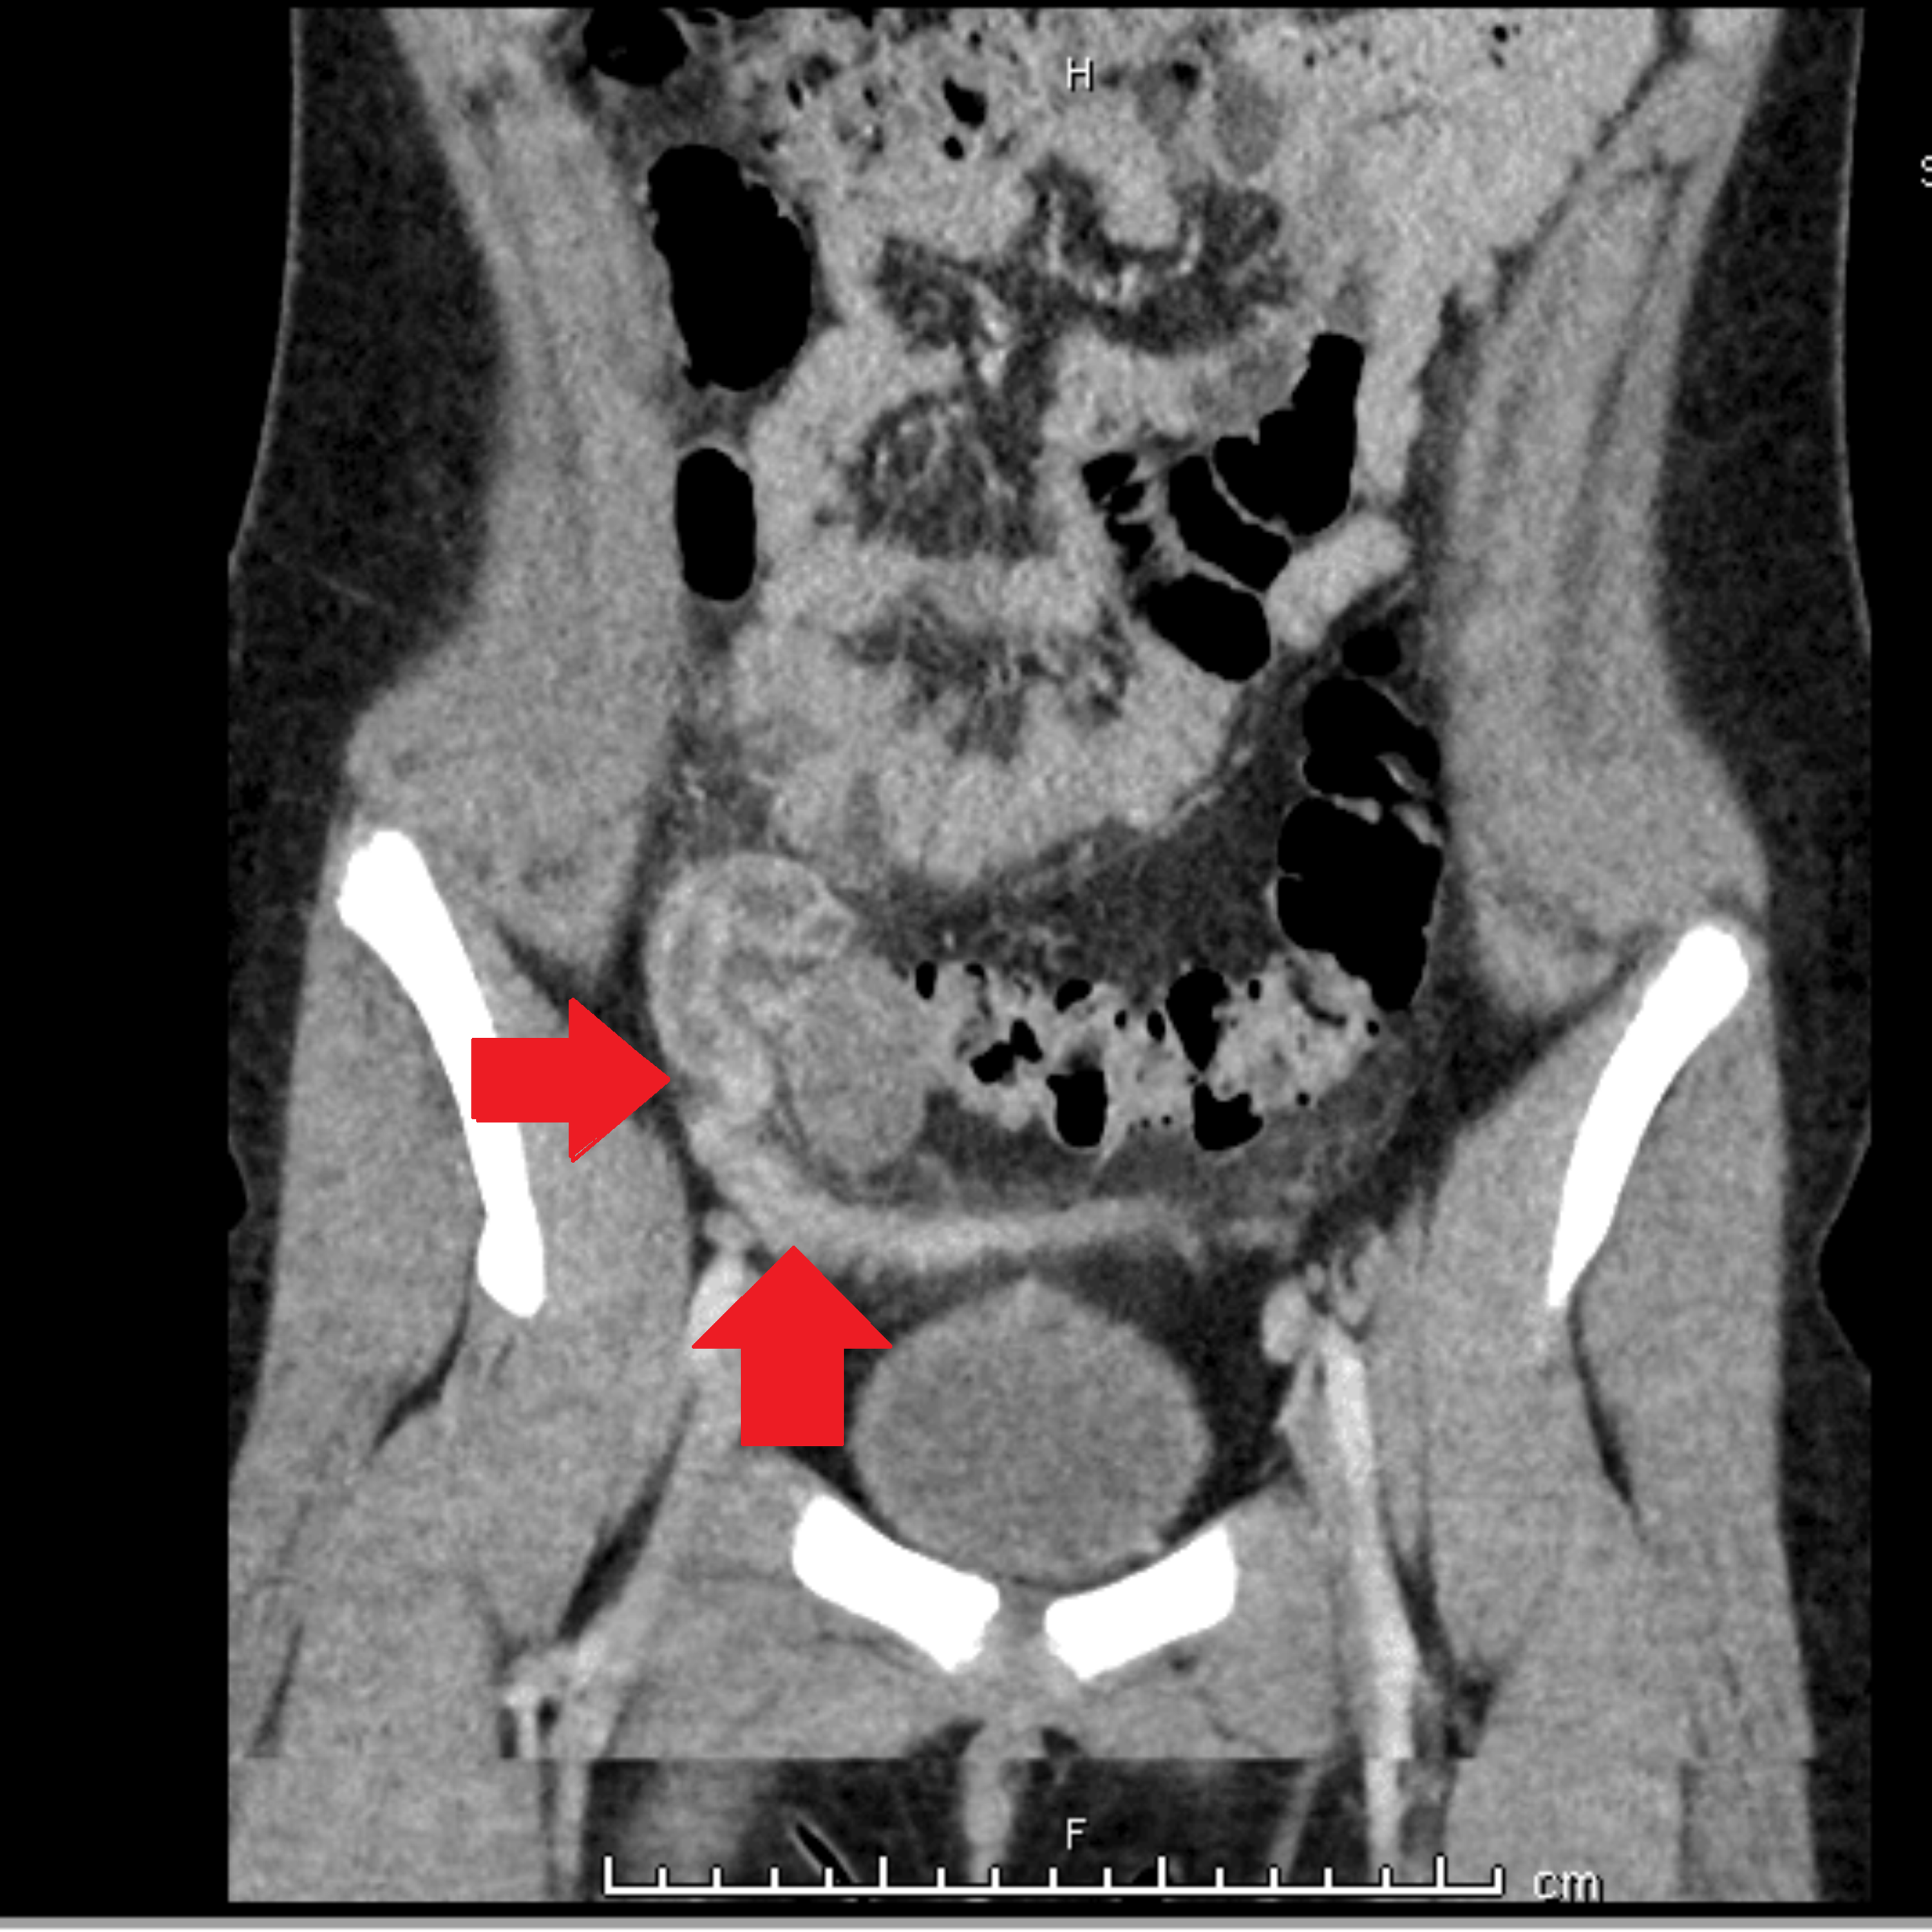

Urachal remnant and a spinning top urethra in a 7yearold female was

Urachal remnant and a spinning top urethra in a 7yearold female was Spinning Top Urethra Treatment Spinning top urethra (stu) is a term used to describe a widened posterior urethra seen mainly in girls. Spinning top urethra (stu) deformity arises secondary to detrusor instability, leading to an increase in the intravesical pressure against a closed sphincter. A spinning top urethra seen on voiding cystograms is diagnostic for dv (fig. 2b) , characterized by dilation of the. Spinning Top Urethra Treatment.